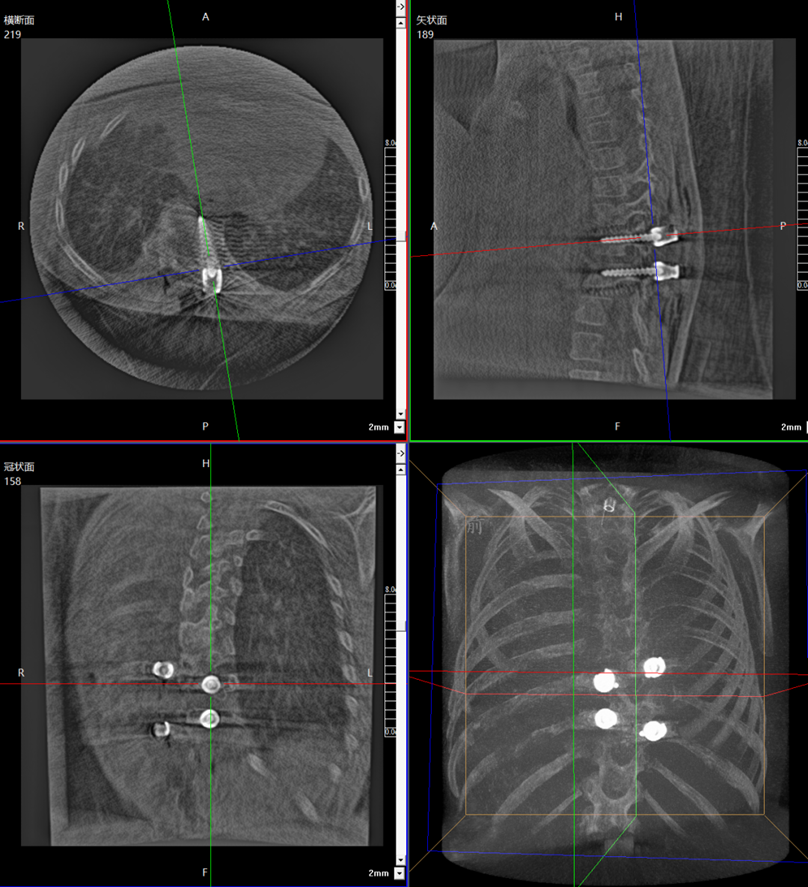

During the surgery, the medical team used the Perlove Medical’s flat-panel 3D C-arm to acquire 3D and CT-like images of the patient, enabling comprehensive visualization of the pedicles. Guided by the robot's 3D planning system, the surgeon mapped each screw's ideal path and angle to achieve maximum screw purchase strength and improve spinal stability by accommodating the unique biomechanical properties of pediatric bone tissue.

The robotic arm enhanced stabilization of surgical instruments, enabling precise execution. Guided by pre-planned trajectories, the system achieved accurate single-attempt pedicle screw placement within narrow vertebral pedicles - effectively navigating the 'anatomical labyrinth'. This approach eliminated risks associated with repeated positioning attempts. The fully integrated system demonstrated perfect coordination, successfully completing the implantation of four pedicle screws with sub-millimeter accuracy.

Fluoro-verified precise screw implantation

Addressing common parental concerns about radiation exposure, traditional K-wire insertion requires separate AP/lateral imaging for each of the four insertion points - with repeated X-ray verification. In contrast, the orthopedic robot utilizes a 'single 3D scan for complete trajectory planning' protocol. When integrated with Perlove Medical's 3D C-arm pulsed fluoroscopy mode, this approach significantly reduces total radiation dosage, effectively mitigating radiation risks.